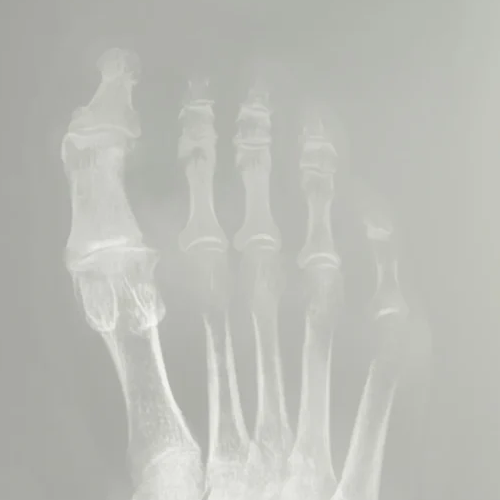

Compare Before & After Result

Before

After